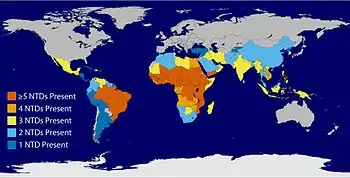

Neglected tropical diseases (NTDs) are a diverse group of tropical infections which are common in low-income populations in developing regions of Africa, Asia, and the Americas.[1] They are caused by a variety of pathogens such as viruses, bacteria, protozoa and parasitic worms (helminths). These diseases are contrasted with the big three infectious diseases (HIV/AIDS, tuberculosis, and malaria), which generally receive greater treatment and research funding.[2] In sub-Saharan Africa, the effect of these diseases as a group is comparable to malaria and tuberculosis.[3] NTD co-infection can also make HIV/AIDS and tuberculosis more deadly.[4]

| Global overlap of six of the common NTDs. Specifically guinea worm disease, lymphatic filariasis, onchocerciasis, schistosomiasis, soil-transmitted helminths, and trachoma in 2011 | |

Twenty neglected tropical diseases are prioritized by the World Health Organization (WHO), though other organizations define NTDs differently. Chromoblastomycosis and other deep mycoses, scabies and other ectoparasites and snakebite envenomation were added to the list in 2017.[11] These diseases are common in 149 countries, affecting more than 1.4 billion people (including more than 500 million children)[12] and costing developing economies billions of dollars every year.[13] They resulted in 142,000 deaths in 2013—down from 204,000 deaths in 1990.[14] Of these 20, two were targeted for eradication (dracunculiasis (guinea-worm disease) by 2015 and yaws by 2020), and four for elimination (blinding trachoma, human African trypanosomiasis, leprosy, and lymphatic filariasis) by 2020.[13]

The six most common NTDs include soil-transmitted helminths (STHs)—specifically roundworm (Ascaris lumbricoides), whipworm (Trichuris trichiura) and hookworms (Necator americanus and Ancylostoma duodenale)—schistosomiasis, trachoma, and lymphatic filariasis (LF).[97] These diseases affect one-sixth of the world's population with 90 percent of the disease burden occurring in sub-Saharan Africa.[97]